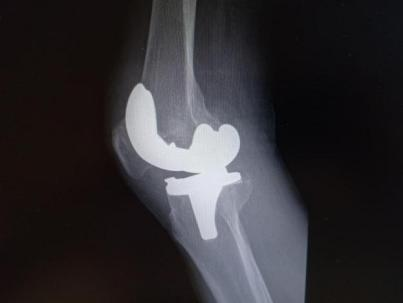

2025年11月1日,由遵义市医学会手外科分会主办、遵义市第二城市医疗集团(贵州航天医院)承办的遵义市医学会手外科分会学术交流会暨贵州省继续医学教育项目《急诊手外伤治疗临床研究新进展专题研讨班》在贵州航天医院成功举办,汇聚了遵义市手外科领域专家及基层医疗骨干,通过专题研讨与临床经验分享,共探急诊手外伤诊疗新进展。 会议特邀遵义市医学会手外科分会主任委员金文虎教授,遵义市医学会手外科分会副主任委员张子阳教授,遵义市医学会手外科分会常务委员杨绍浦教授,贵州航天医院陈明勇教授、赵兴东教授等遵义市手外伤专家进行交流分享;贵州航天医院党委委员、副院长彭亮参加会议并致辞,贵州航天医院骨科医务人员,遵义市第二城市医疗集团成员单位及红花岗区、绥阳县、桐梓县等区县医疗机构手外伤骨干参与。 贵州航天医院党委委员、副院长彭亮致辞 学术交流 本次学术交流以“急诊手外伤治疗临床研究新进展”为主题,通过理论授课与临床案例结合,共同探讨急诊手外伤临床诊疗全链条诊疗策略、关键技术、临床研究新进展,促进规范化诊疗技术向基层下沉,助力提升区域手外伤应急处置与修复能力。 贵州航天医院赵兴东教授分享《急诊手外伤的诊断与治疗原则》 贵州航天医院陈明勇教授分享《开放性骨折的治疗原则》 贵州航天医院张军教授分享《甲沟炎Winograd手术的临床应用》 贵州航天医院赵兴东教授分享《手部常见的皮肤缺损及治疗原则》 贵州航天医院张艳金教授分享《开放性骨折的清创术》 贵州航天医院冷家雄教授分享《下肢创面修复的常用皮瓣之股前外侧皮瓣》 贵州航天医院邬夏荣教授分享《踝关节慢性不稳的诊治》 贵州航天医院卢懿明教授分享《掌骨骨折》 贵州航天医院张艳金教授分享《手部肌腱的解剖与修复方法》 本次研讨班为遵义市手外科领域医务人员提供了深度交流契机,强化了医疗机构间的协作网络,进一步推动学科创新与临床实践融合,为健康遵义建设注入新动能。 贵州航天医院骨科专家简介 陈明勇 骨一科主任,副主任医师 临床擅长:从事创伤骨科工作约20年,对骨缺损、骨不连、骨肿瘤、肢体畸形等的肢体矫形重建及功能重建,慢性化脓性骨髓炎的根治治疗、糖尿病足的保肢治疗、快速康复理念(ERAS)下的老年骨折的诊治,四肢复杂骨折的诊治,四肢骨折等微创手术治疗具有丰富的临床经验。 2004年毕业于遵义医学院临床专业,曾在中国人民解放军总医院、广西医科大学第一附属医院、上海第六人民医院骨科进修。中国中西医结合学会骨伤科专业委员会横向骨搬移治疗糖尿病足及微血管网再生学组首届委员,遵义市医学会创伤分会常务委员。 瞿 晖 骨科党支部书记,骨二科主任,副主任医师 临床擅长:对骨科的常见病、关节外科、脊柱外科及运动医学疾病的诊治具有丰富的临床经验,熟练掌握骨科手术操作技术。 毕业于遵义医学院临床医学系,2005年前往广州中山大学第一附院骨显微医学部进修学习,2011年前往成都华西医院进修学习,并多次在省内外学习骨科相关知识,是中华医学会骨科分会会员。 赵小锋 中共党员,骨二科副主任,副主任医师 临床擅长:从事骨科临床工作11年,对骨科常见病、多发病诊疗有较为丰富的临床经验,擅长脊柱相关疾病诊断及治疗,尤其是颈、腰、腿疼痛疾病诊断及治疗,擅长胸腰椎骨折微创经皮穿刺内固定术、经皮穿刺椎体成形术、经皮穿刺脊柱内镜下腰椎间盘摘除术、单纯开创腰椎间盘摘除术、腰椎滑脱复位椎间植骨椎融合内固定术、腰椎管狭窄减压融合内固定术及人工髋、膝关节置换术等。 2012年毕业于遵义医学院外科学专业硕士研究生,2019年参加“遵义市115医学人才精英计划”于上海交通大学第一附属医院培训学习,2023年于北京大学第三人民医院脊柱外科进修学习,曾获得遵义市优秀医师荣誉称号。 遵义市手外科第一届委员,遵义市医学会创伤分会第一届委员,遵义市医学会创伤分会第二届委员,贵州省康复医学会第三届脊柱脊髓专业会委员,遵义市医学会烧伤与整形外科学分会委员,发表论文5篇,其中国家级核心期刊1篇,SCI论文1篇,主持市级课题1项并结题,参与市级课题2项。 赵兴东 骨科主任医师 临床擅长:擅长骨科的常见病及各种创伤、四肢骨折创伤修复、骨感染、手足疾病的诊治和手足体表畸形的矫形整复,熟练掌握骨科四肢骨病及创伤的手术操作技术,尤其在四肢关节复杂性损伤、手足外伤、组织缺损创面、难治创面的皮瓣修复方面及平足、高弓足矫形方面及四肢慢性疼痛诊治、康复方面具有丰富的临床经验。 硕士研究生,毕业于遵义医学院临床外科系,2015年前往山东省立医院手足外科进修学习;遵义市医学分会创伤分会第一、二届委员,遵义市手外科医学会第二委届员会常务委员;在省级及省级以上期刊发表文章9篇,参编著作2部,参与主持并完成市级课题1项,参与市级课题2项、省级课题1项。 张艳金 中共党员,骨科副主任医师 临床擅长:从事骨外科工作16年,对复合伤、多发伤的救治、四肢骨干骨折、关节周围骨折、骨肿瘤、骨髓炎等诊治具有丰富的临床经验。 中共党员,硕士研究生,2006年本科毕业于山西医科大学第二临床医学院,2011年研究生毕业于北京军区总医院;在“老年COPD患者合并髋部骨折的诊治”国际合作课题组研究两年,在老年髋部骨折的诊治方面具有丰富的经验,并发表论文6篇;主持遵义市级课题1项,承担遵义医科大学的临床教学工作,获得遵义医科大学优秀带教老师荣誉。编撰有《骨科疾病诊疗精粹》一书,开展2项新技术,编撰地方规范《务川自治县创伤骨科常见疾病诊疗规范》一书。 张俊凯 骨科副主任医师 临床擅长:从事骨科临床工作28年,对创伤骨折、骨感染、骨缺损、骨不连等外科诊治,四肢骨折的微创手术治疗,四肢复杂骨折(如关节内粉碎性骨折、多发骨折等)的损伤控制及手术治疗等具有丰富的临床经验。 1995年毕业于遵义医学院临床专业,2009年前往复旦大学附属医院骨科进修1年。 卢懿明 中共党员,骨科副主任医师 临床擅长:从事骨科工作18年,对创伤骨折、四肢骨折的微创手术治疗、四肢复杂骨折(如关节内粉碎性骨折、多发骨折等)的损伤控制及手术治疗,尤其是髋部骨折的PFNA等微创技术,踝关节骨折、膝关节周围骨折的Mipo微创技术等具有丰富的临床经验,开展了4项新技术,发明6项新型专利技术。 2005年毕业于遵义医学院临床专业,2017年,前往南方医科大学第三附属医院骨科进修半年,回院后运用Mipo技术对骨干骨折及干骺端骨折的治疗技术,同时积极开展骨盆骨折、髋臼骨折腹直肌外侧切口的应用;发表了多篇专业论文,经常参与省内外学术交流会授课,获得医院荣誉称号多个。 邬夏荣 骨科副主任医师 临床擅长:从事骨科工作16年,对四肢复杂骨折、骨肿瘤的诊治,尤其是足踝创伤、慢性踝关节损伤、平足症等诊疗具有丰富的临床经验。 2006年毕业于遵义医科大学临床医学专业,曾在陆军军医大学西南医院进修学习,发表多篇骨科学术论文。 余德怀 中共党员,骨科副主任医师 临床擅长:从事骨科工作10余年,对运动医学、骨关节、脊柱外科常见病、多发病的诊治具有丰富的临床经验。 硕士研究生,2011年毕业于遵义医学院临床医学专业,曾前往遵义医科大学附属医院运动医学专业进修学习;是贵州省医学会运动医学分会青年委员,西部关节镜联盟委员;发表多篇骨科学术论文。 冯 乾 骨科副主任医师 临床擅长:从事骨科工作近20年,熟练掌握骨科多发病及常见病的诊治,尤其对脊柱退变性疾病的诊断及治疗具有丰富的临床经验,主要研究脊柱微创相关治疗方式,能熟练开展椎间孔镜及UBE。 曾前往北京大学第三医院进修学习疼痛及椎间孔镜、首都医科大学友谊医院专业进修脊柱内镜;是贵州省康复医学会第三届脊柱脊髓专业委员会委员;发明专利3项、发表脊柱外科专业论文多篇。 贵州航天医院骨科简介 基本情况 贵州航天医院(原3417医院)骨科组建于1968年,前身是以创伤和断肢(断指)再植闻名于世的上海市第六人民医院骨科,中国断肢(断指)再植的奠基者、中科院院士陈仲伟等专家莅临科室指导医疗和教学,并在70年代开展了贵州省首例断肢(断指)再植手术。组建50余年来,诊治患者已逾百万,挽救了无数的伤病员,成为了保障遵义地区人民群众健康的重要支撑。 经过几代人的不懈努力,今天的骨科,已由创伤骨科发展至骨病、骨肿瘤、骨结核等领域,现有脊柱外科、关节外科、四肢创伤、手足外科四个亚专科,成为了集医疗、教学、科研于一体的综合学科,是贵州省临床重点专科、遵义市临床重点专科、遵义市骨科临床医学中心、遵义市基层骨科专科联盟理事长单位。 科室目前开放床位110张,共有医护人员50余人,副高级以上专家18人,硕士研究生15人。拥有一流骨科医疗设备多台,每年不定期选派优秀技术骨干到全国各大知名医学院校进修、学习、参观、交流,并邀请国内、国外知名专家教授来院进行交流、指导,通过不断引进国内外先进的诊疗技术,科室医疗技术水平稳步提升,为广大人民群众提供了优质的医疗服务。 专科特色 骨一科 (一)骨缺损、骨不连的肢体与功能重建 胫骨横向骨搬移技术治疗糖尿病足: (二)慢性骨髓炎的根治治疗 (三)肢体缺血性疾病如糖尿病足、脉管炎的保肢治疗 (四)皮瓣修复 (五)复杂创伤的治疗 (六)老年髋部骨折及小儿骨折快速手术 老年髋部骨折: 骨二科 (一)胸腰椎骨折微创经皮椎弓根螺钉固定术 (二)老年性骨质疏松性患者腰椎滑脱脊柱内固定术(骨水泥螺钉) (三)V形双通道脊柱内镜技术(VBE)腰椎融合术治疗腰椎退行性疾病 (四)老年性骨质疏松性骨折(PVP/PKP)术 (五)人工髋关节置换术 (六)双侧股骨头坏死人工全髋关节置换 (七)右侧全髋置换术后假体周围骨折翻修 (八)人工膝关节置换术 (九)人工膝关节假体松动翻修 (十)关节镜技术 传统手术切口 关节镜技术切口 诊疗范围 骨一科 1.四肢创伤、矫形。 2.手、足踝外科。 骨二科 End